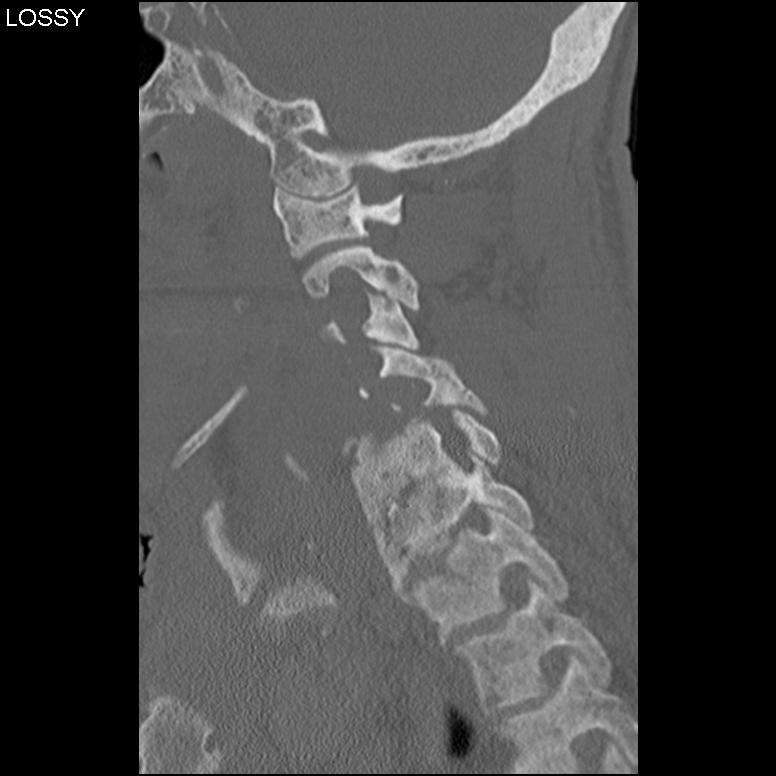

CT

Soft tissue involvement

Good for TB